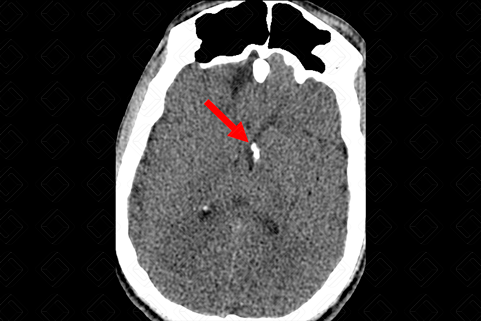

Texto alternativo para a imagem Figura 1. Créditos: Dra. Elazir Mota - Rio de Janeiro/RJ

Descrição das figuras 1 e 2: Tomografia computadorizada do crânio. Presença de nódulos subependimários calcificados – setas vermelhas (a calcificação deles permite a visualização na tomografia computadorizada). [cms-watermark]

• Nódulos subependimários: Representam hamartomas em crescimento e, comumente, são observados nesse grupo de pacientes. São lesões benignas, mas que podem degenerar para os astrocitomas de células gigantes. Caracterizam-se na tomografia de crânio em cerca de 88% dos casos e isso se deve ao fato da maioria deles serem calcificados nos estudos de imagem. Na ressonância apresentam sinal intermediário em T1 e iso a hipersinal em T2 (figuras 1 e 2);